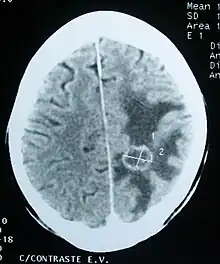

Imaging

Medical imaging plays a central role in the diagnosis of brain tumors. Early imaging methods – invasive and sometimes dangerous – such as pneumoencephalography and cerebral angiography have been abandoned in favor of non-invasive, high-resolution techniques, especially magnetic resonance imaging (MRI) and computed tomography (CT) scans,[38] though MRI is typically the reference standard used.[41] Neoplasms will often show as differently colored masses (also referred to as processes) in CT or MRI results.

- Benign brain tumors often show up as hypodense (darker than brain tissue) mass lesions on CT scans. On MRI, they appear either hypodense or isointense (same intensity as brain tissue) on T1-weighted scans, or hyperintense (brighter than brain tissue) on T2-weighted MRI, although the appearance is variable.

- Contrast agent uptake, sometimes in characteristic patterns, can be demonstrated on either CT or MRI scans in most malignant primary and metastatic brain tumors.

- Pressure areas where the brain tissue has been compressed by a tumor also appear hyperintense on T2-weighted scans and might indicate the presence of a diffuse neoplasm due to an unclear outline. Swelling around the tumor known as peritumoral edema can also show a similar result. This is because these tumors disrupt the normal functioning of the BBB and lead to an increase in its permeability.

Computed Tomography (CT) Scan – uses x-rays to take pictures from different angles and computer processing to combine the pictures into a 3D image. A CT scan usually serves as an alternative to MRI in cases where the patient cannot have an MRI due to claustrophobia or pacemaker. Compared to MRI, a CT scan shows a more detailed image of the bone structures near the tumor and can be used to measure the tumor’s size.[48] Like an MRI, a contrast dye may also be injected into the veins or ingested by mouth before a CT scan to better outline any tumors that may be present. CT scans use contrast materials that are iodine-based and barium sulfate compounds. The downside of using CT scans as opposed to MRI is that some brain tumors do not show up well on CT scans because some intra-axial masses are faint and resemble normal brain tissue. In some scenarios, brain tumors in CT scans may be mistaken for infarction, infection, and demyelination. To suspect that an intra-axial mass is a brain tumor instead of other possibilities, there must be unexplained calcifications in the brain, preservation of the cortex, and disproportionate mass effect.[49]